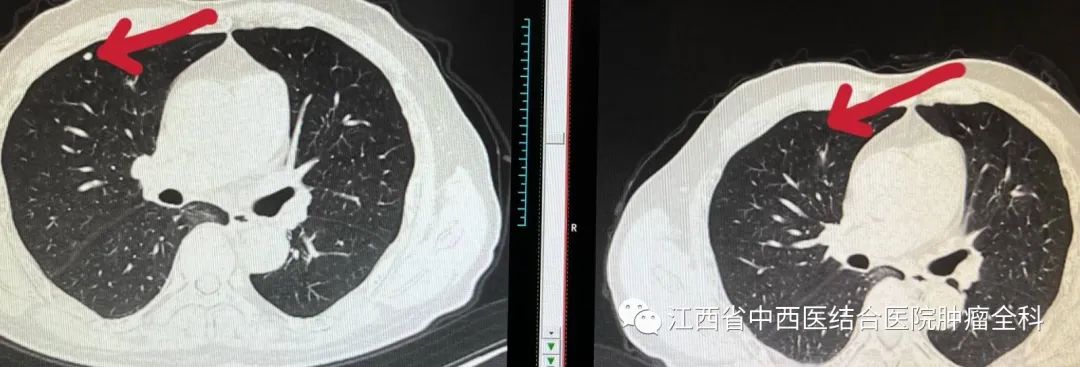

图5-7:2022年2月07日与2022年5月17日胸部CT结节影治疗前后对比

胸部CT: 双肺多发结节转移灶较前缩小,部分消失。

胸部CT: 双肺多发微结节灶已消失。